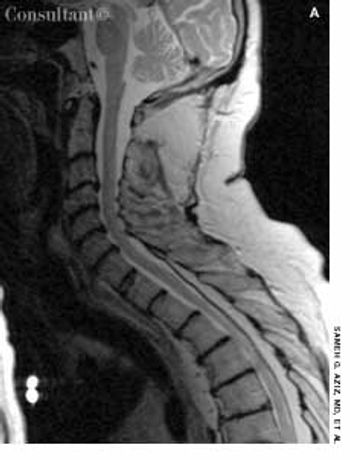

A 62-year-old man who was receiving long-term corticosteroid therapy for Wegener granulomatosis presented with progressive leg weakness over 1 week. He had the stigmata of Cushing syndrome: moon facies, truncal obesity, and a dorsocervical fat pad.